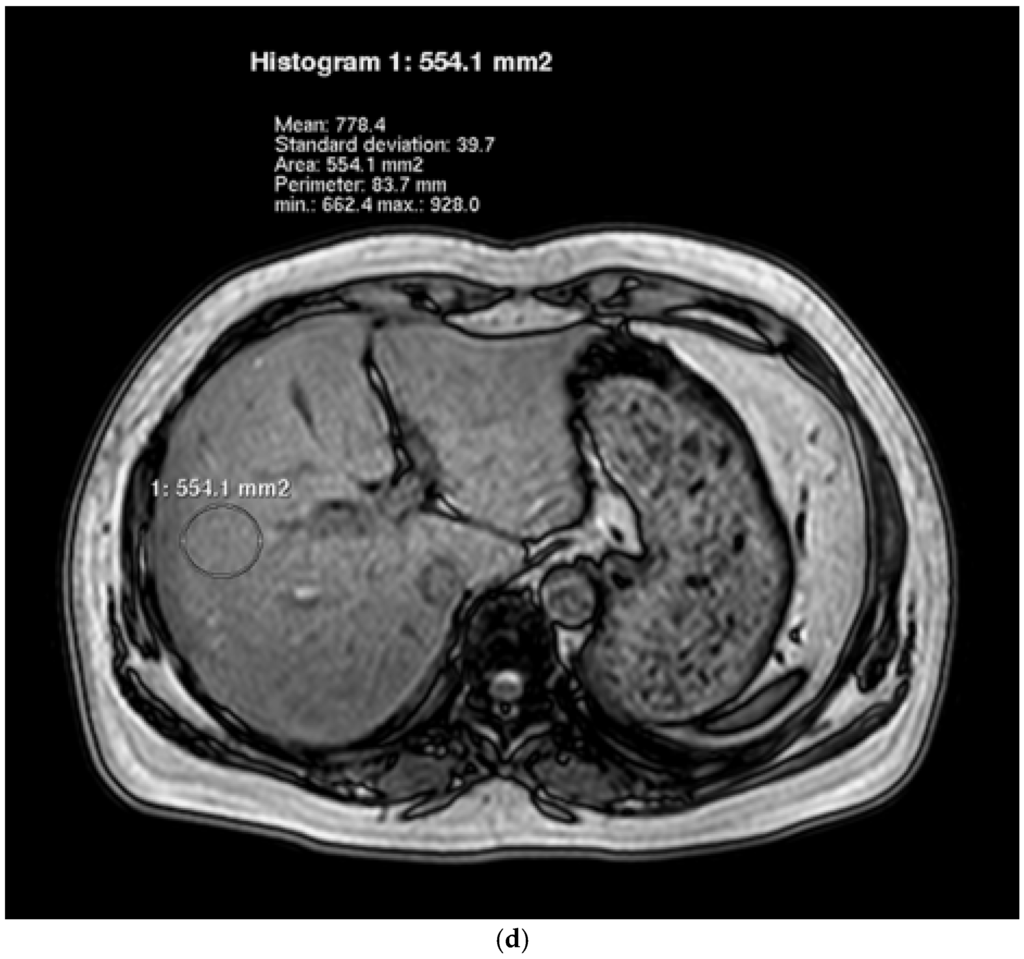

Associations between Dietary Nutrient Intakes and Hepatic Lipid Contents in NAFLD Patients Quantified by 1H-MRS and Dual-Echo MRI

by Yipeng Cheng, Kewei Zhang, Yang Chen, Yanchuan Li, Yuzheng Li, Kuang Fu and Rennan Feng

Nutrients 2016, 8(9), 527; https://doi.org/10.3390/nu8090527 - 27 Aug 2016

Dietary habits are crucial in the progression of hepatic lipid accumulation and nonalcoholic fatty liver disease (NAFLD). However, there are limited studies using 1H-magnetic resonance spectroscopy (1H-MRS) and dual-echo in-phase and out-phase magnetic resonance spectroscopy imaging (dual-echo MRI) to assess [...] Read more.

Dietary habits are crucial in the progression of hepatic lipid accumulation and nonalcoholic fatty liver disease (NAFLD). However, there are limited studies using 1H-magnetic resonance spectroscopy (1H-MRS) and dual-echo in-phase and out-phase magnetic resonance spectroscopy imaging (dual-echo MRI) to assess the effects of dietary nutrient intakes on hepatic lipid contents. In the present study, we recruited 36 female adults (NAFLD:control = 19:17) to receive questionnaires and medical examinations, including dietary intakes, anthropometric and biochemical measurements, and 1H-MRS and dual-echo MRI examinations. NAFLD patients were found to consume diets higher in energy, protein, fat, saturated fatty acid (SFA), and polyunsaturated fatty acid (PUFA). Total energy intake was positively associated with hepatic fat fraction (HFF) and intrahepatic lipid (IHL) after adjustment for age and body-mass index (BMI) (HFF: β = 0.24, p = 0.02; IHL: β = 0.38, p = 0.02). Total fat intake was positively associated with HFF and IHL after adjustment for age, BMI and total energy intake (HFF: β = 0.36, p = 0.03; IHL: β = 0.42, p = 0.01). SFA intake was positively associated with HFF and IHL after adjustments (HFF: β = 0.45, p = 0.003; IHL: β = 1.16, p = 0.03). In conclusion, hepatic fat content was associated with high energy, high fat and high SFA intakes, quantified by 1H-MRS and dual-echo MRI in our population. Our findings are useful to provide dietary targets to prevent the hepatic lipid accumulation and NAFLD. Full article